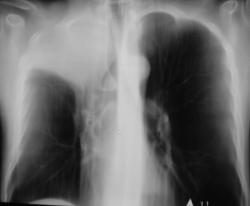

Иллюстрации 4, 5. На обзорной рентгенограмме органов грудной полости, произведенной в прямой проекции, в дополнении к скиалогической картине, полученной при цифровой флюорограмме добавлено — некоторое смещение верхнего средостения вправо с учетом смещения «просвета трахеи». При детальном исследовании области правого корня дополнительной информации не выявлено.